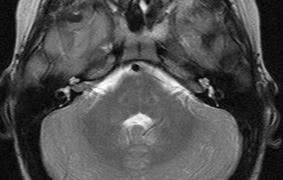

OPTIC NERVE GLIOMAS

Optic pathway gliomas arise from the astrocytes of the optic nerve. Most are pilocytic astrocytomas and typically remain intradural, extending in the subdural space. Malignant transformation is rare. There appear to be two growth patterns62:

- Perineural growth pattern, correlating with a diagnosis of NF1. The tumor expands in the subarachnoid

space and the optic nerve is compressed as a central ribbon. On

T2-weighted MRI, this may be seen as a low-intensity core with surrounding

high-intensity rim. Increased tortuosity of the optic nerve is also

associated with this growth pattern (Fig. 5).63

- Intraneural growth pattern, correlating with the absence of NF1.

The incidence of optic pathway gliomas in NF1 is difficult to estimate, as the majority are asymptomatic and do not affect vision. In NF1, radiographic evidence of an optic nerve glioma occurs in 15% of patients.64,65 Most tumors are neither suspected historically nor detected by ophthalmic examination.65 Even when optic nerve gliomas become clinically detectable, visual function often remains stable in the absence of any intervention.66,67 Thus routine computed tomography (CT) imaging, even in patients with a known optic nerve glioma, is controversial. The potential risks of repeated radiation exposure in a child with a tumor-suppressor gene defect is a consideration. MRI studies are more revealing than CT but may require sedation or anesthetic and are costly. An MRI is often recommended at the time of diagnosis, but in most cases routine “follow-up” MRIs are unnecessary. Annual ophthalmic clinical examination for relative afferent pupillary defect (RAPD), visual acuity, visual fields, color vision, and funduscopy is usually all that is required, as no therapeutic action is likely to be taken unless there is significant and progressive visual involvement.

Optic nerve gliomas may involve the optic chiasm and be associated with endocrine disorders or nystagmus.68–70 Surgical excision of chiasmal gliomas (Fig. 6) carries a high risk of visual loss. Invasion of the hypothalamus or the third ventricle carries a poor prognosis, with greater than 50% 15-year mortality rate.71 One review of radiation treatment for chiasmal gliomas collated data from small case series and found no significant long-term improvement in visual function, progression, or mortality with radiation treatment.71 Other reports suggest that radiation doses over 4500cGy improve symptoms and slow progression of chiasmal gliomas over several years.72 Adequate tumor coverage by radiotherapy results in irradiation of normal brain and nearly all children need hormone replacement.73 Chemotherapy is an alternative.74,75

|

- Optic glioma (Fig. 5)